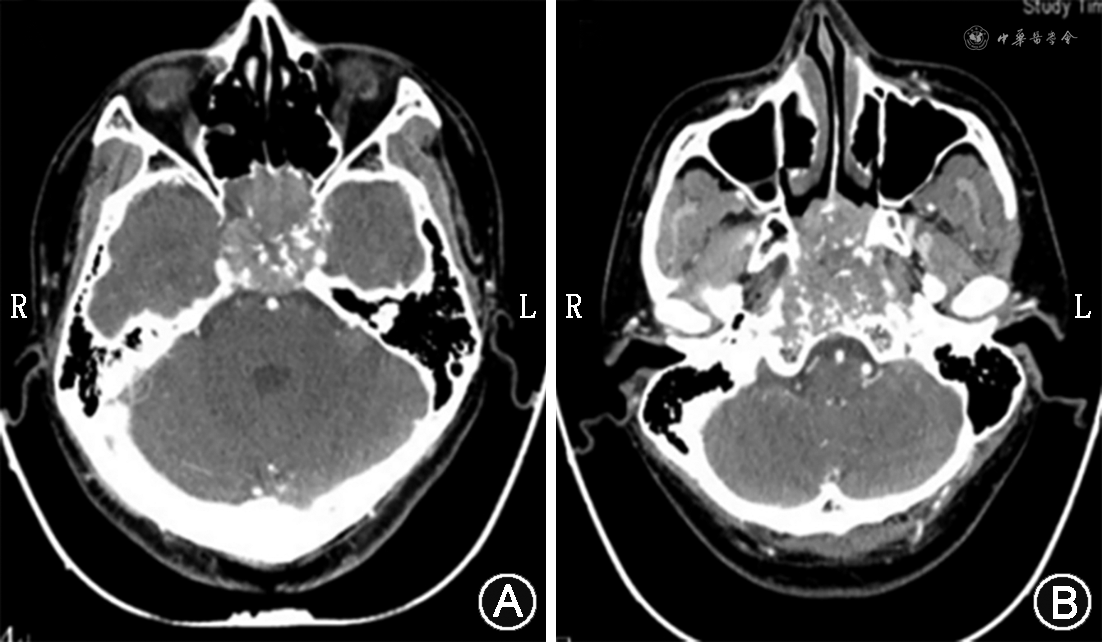

鼻咽癌侵犯颅底、颅内时,CT检查通常表现为[29]:①颅底骨质边界不完整,骨皮质不连续或点片状骨质缺损;②颅底自然孔道如破裂孔、卵圆孔、棘孔破坏或不规则扩大;③颅内脑膜外出现等密度、稍高密度或稍低密度结节样及条片样软组织影,增强扫描病灶强化程度与鼻咽部病灶一致;④局部脑膜增厚,增强扫描呈明显强化;⑤海绵窦不规则扩大,增强扫描呈异常强化(图3)。

鼻咽癌侵犯颅底、颅内时,MRI检查通常表现为[28]:①颅底骨质不连续,正常骨髓脂肪高信号消失,出现不规则斑片状异常低信号影,骨质破坏区域边界不清,增强扫描可见其异常强化;②颅内脑膜外局部肿物,T1WI呈稍低信号,T2WI呈稍高信号,T2 STIR序列病灶信号明显增高,病灶强化显著;③神经通路上出现异常肿块,T1WI呈稍低信号,T2WI呈稍高信号,相应神经根增粗、强化;④颅底自然孔道破坏或不规则扩大;⑤非对称海绵窦扩大,受累海绵窦可见弥散性或局限性增厚,且异常强化(图4)。